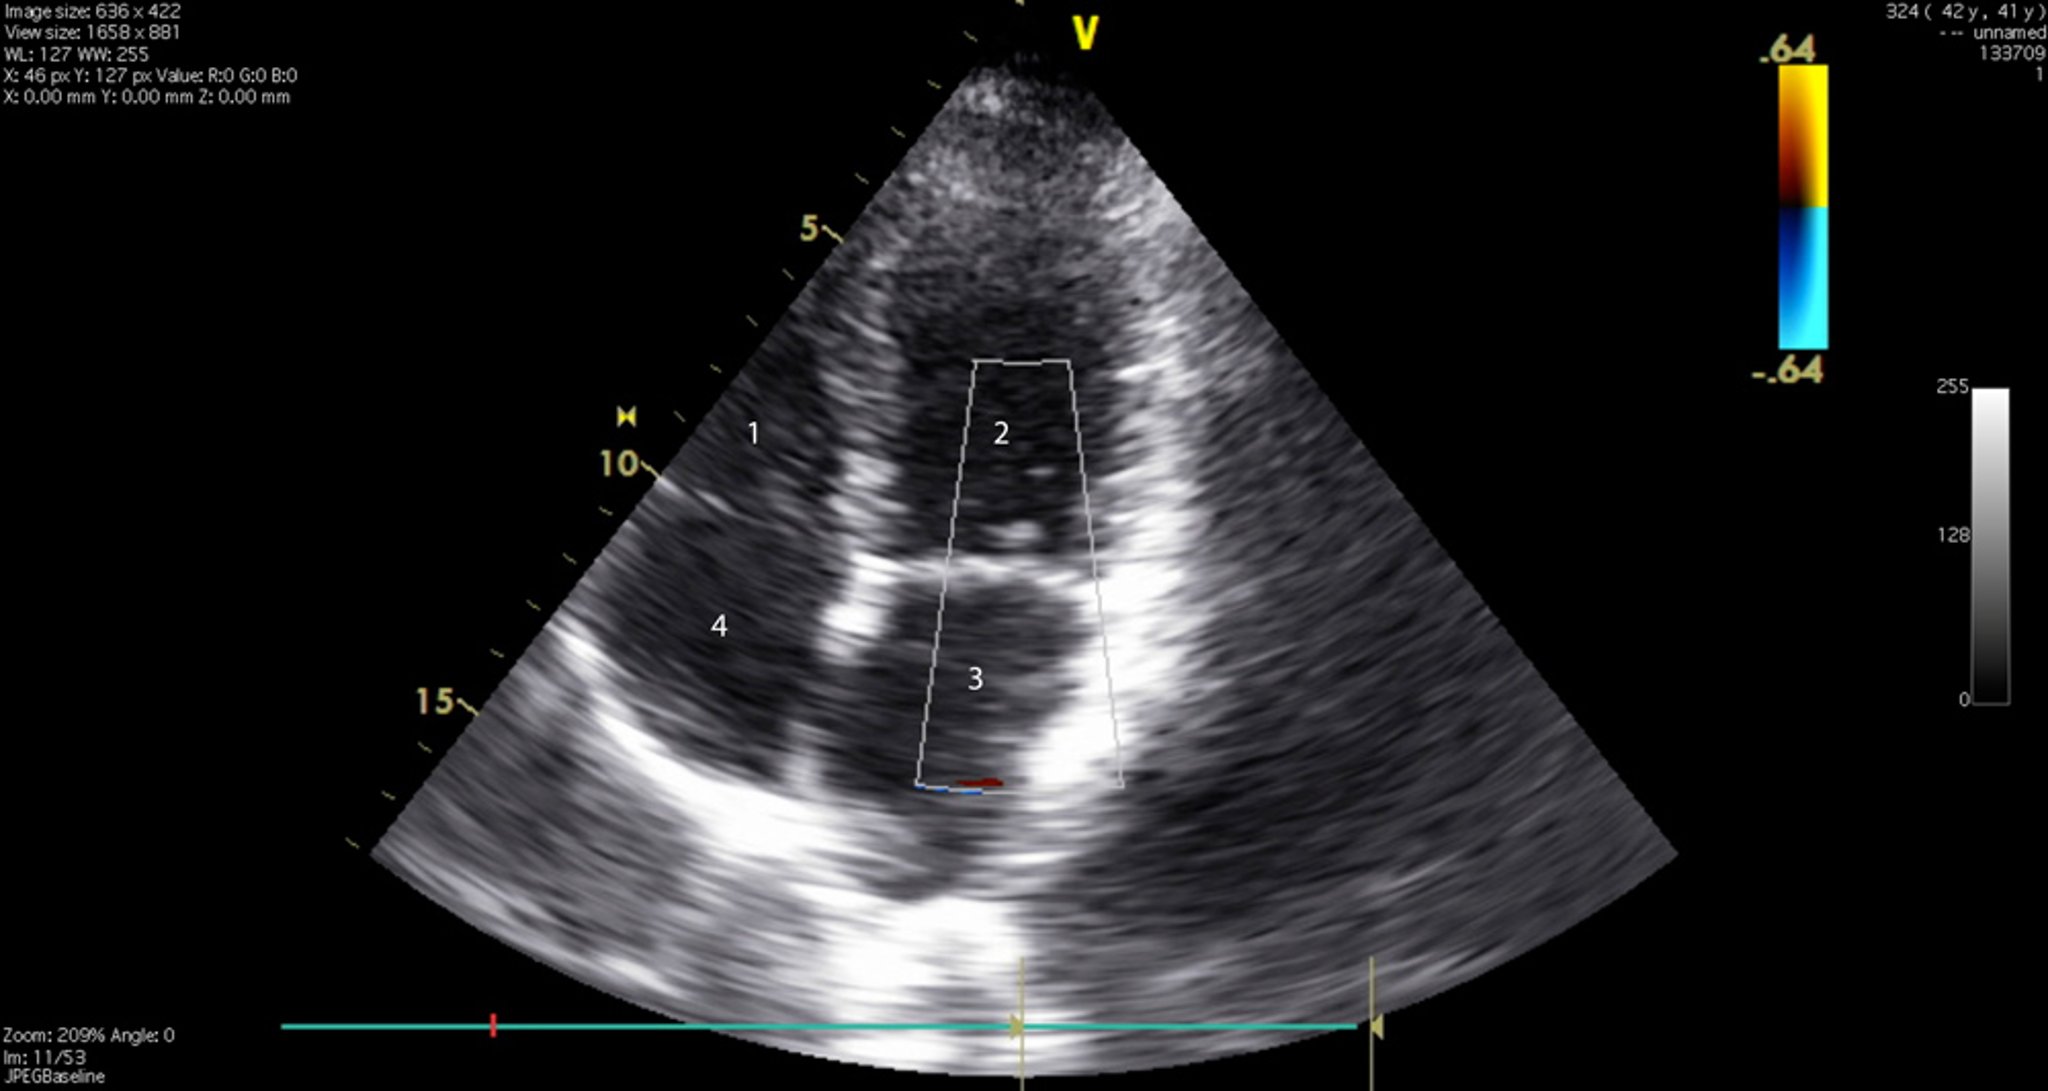

Échocardiogramme (vue des 4 cavités)

Cette image montre les 4 cavités cardiaques et les valvules tricuspidienne et mitrale. 1 = ventricule droit; 2 = ventricule gauche; 3 = oreillette gauche; 4 = oreillette droite.